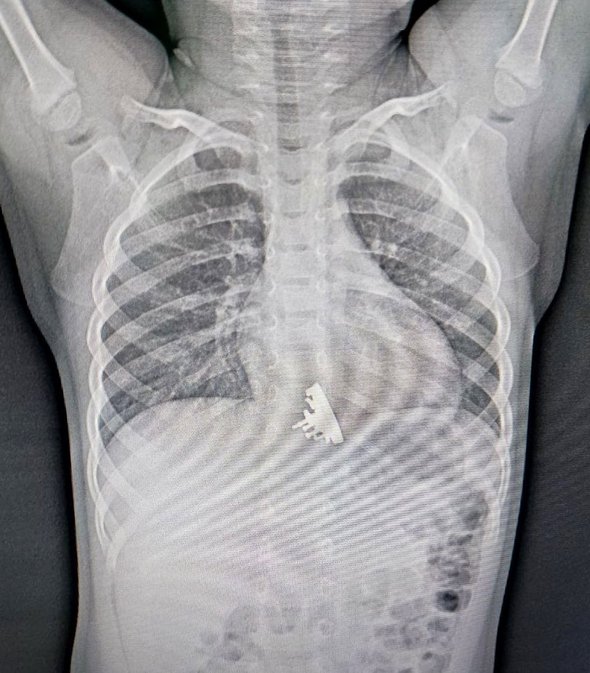

Со слов родителей ребенка, сначала они заметили, что дочь поперхнулась, начала подкашливать и беспокойно себя вести. Самостоятельно выяснить причину такого поведения они не смогли и решили обратиться к медикам. Родители приехали с девочкой в приемное отделение ОГАУЗ ГИМДКБ и описали им свои наблюдения. Рентген снимок показал наличие инородного тела в нижней трети пищевода ребенка, судя по очертаниям предмета, ребенок проглотил игрушечный кораблик из набора конструктора.

Врачи решили немедленно провести эзофагогастродуоденоскопию, так застрявший в пищеводе крейсер «Аврора» травмировал слизистую внутренних органов. «Мы сразу обратили внимание, что у инородного тела есть достаточно острые выступающие части, которые цеплялись за стенки пищевода и царапали его», — рассказал врач отделения эндоскопии Ивано-Матренинской детской клинической больницы Илья Пикало.